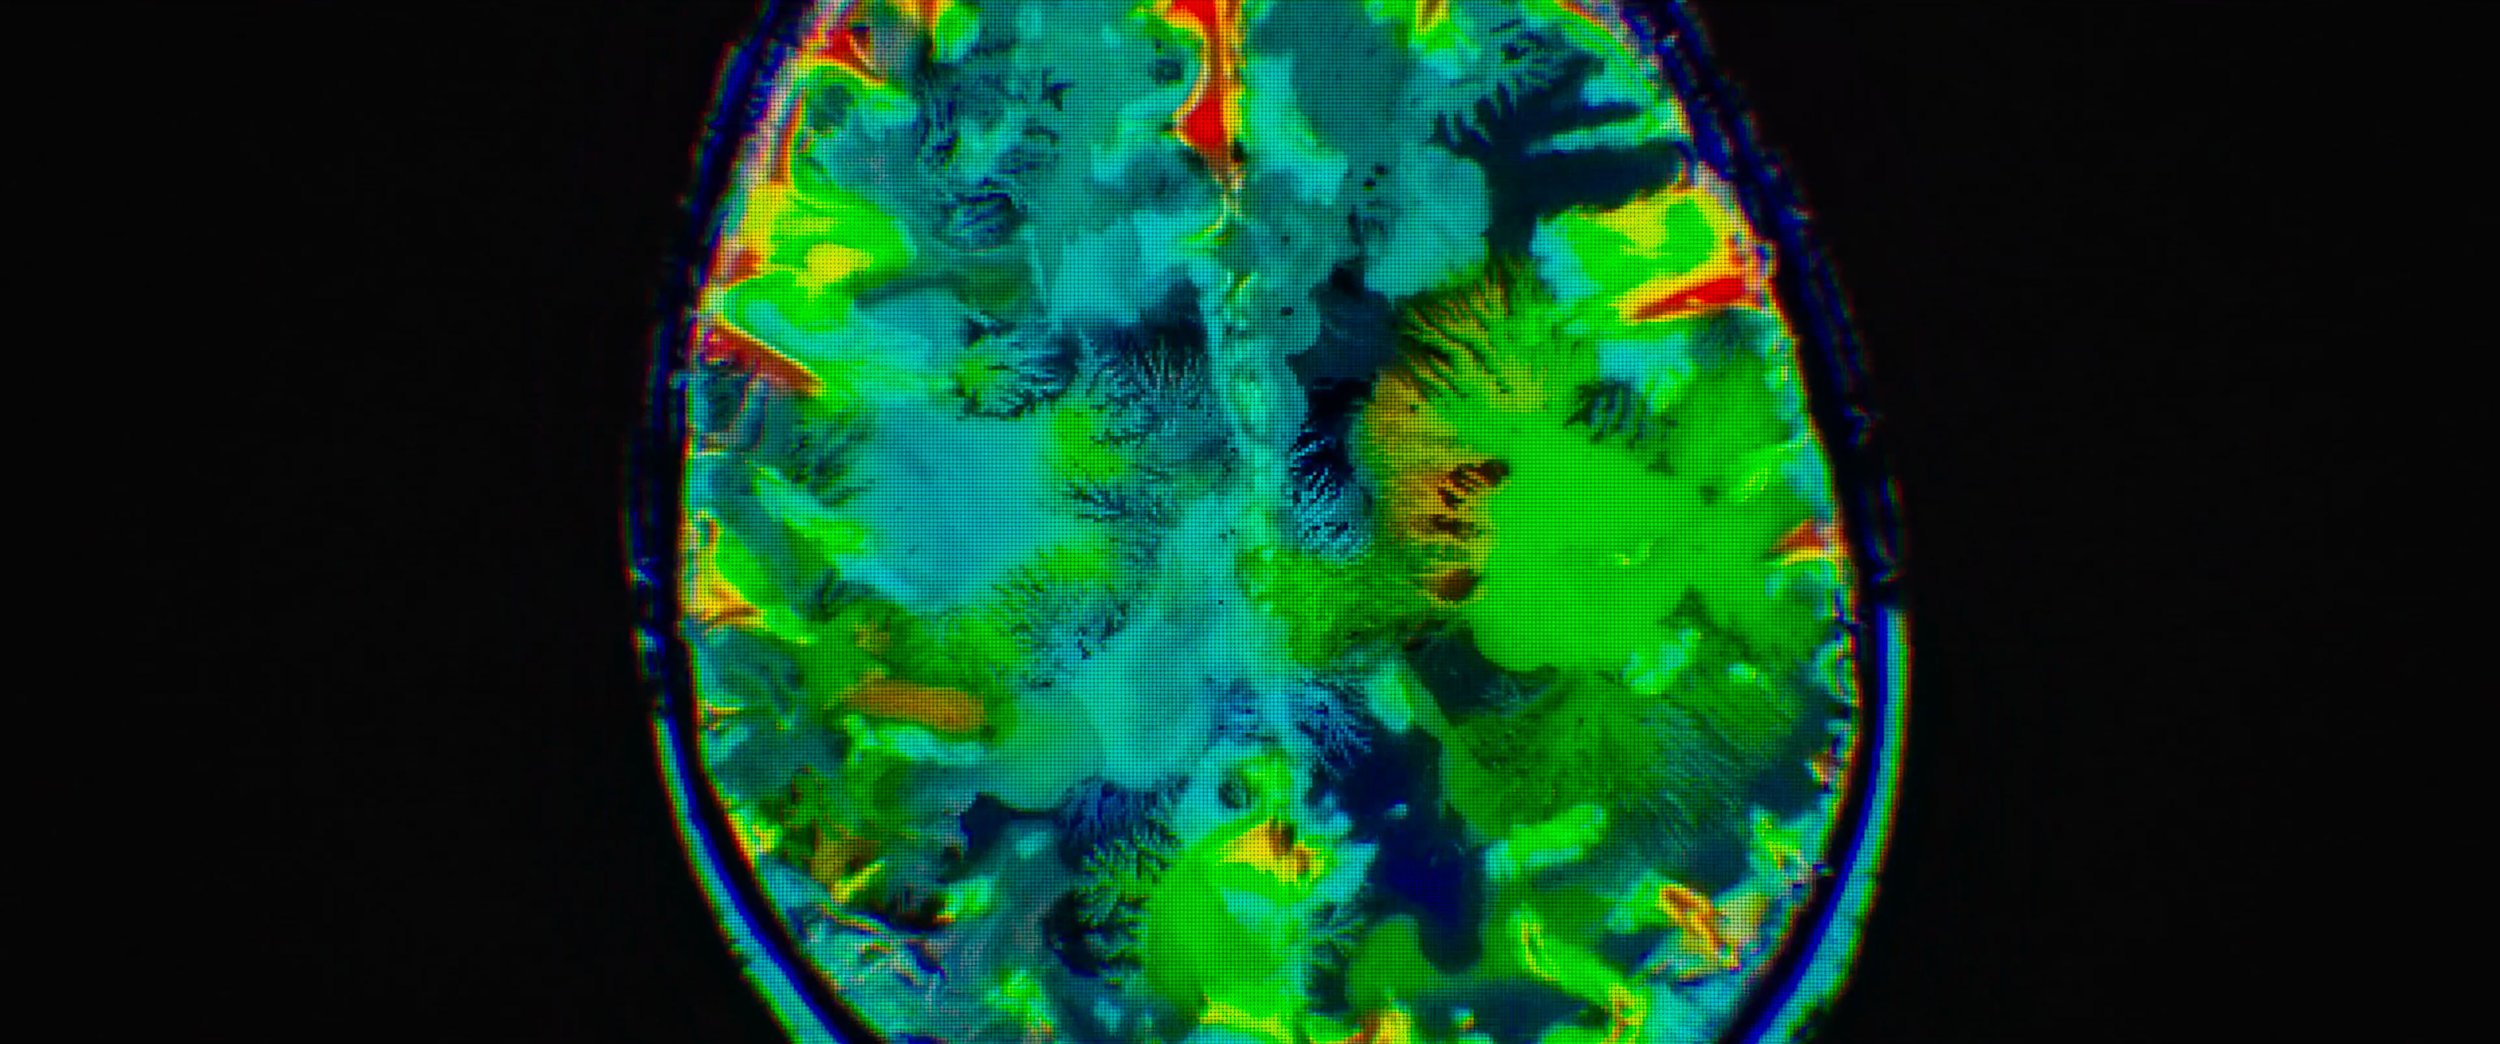

FIVE DAYS AT MEMORIAL

MAIN TITLE SEQUENCE

Role: Edit, Type Animation, Motion Design, & Compositing

Five Days at Memorial is an American disaster medical drama television miniseries based on the 2013 book of the same name. The series depicts the extreme difficulties a New Orleans hospital endures after Hurricane Katrina makes landfall on the city. The miniseries premiered on August 12, 2022, on Apple TV+.

Working again with Me & The Bootmaker and with videographer Roman Hill, I was brought in to handle compositing, edit, typography animation, and overall motion design.